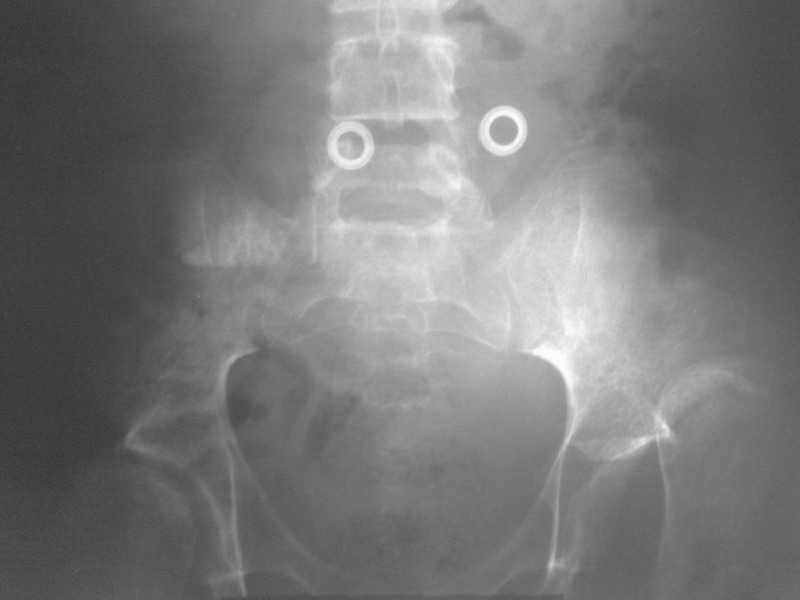

Под общим наркозом вправлен. 2 недели ребенок находился на лейкопластырном вытяжении. В связи с тяжким состоянием ребенка (диспептические явления, задержка стула, носовые кровотечения, начальные явления застойной пневмонии) вытяжение снято. сразу после чего сделано рентген контроль (фото 1). а через неделю, то есть сегодня сделан второй снимок (фото 2). Где видно повторный вывих.

На рентгенограмме видно, что в 3 месячном возрасте не была диагностирована тяжелая форма дисплазии с подвывихами, где, кроме вывиха, имеет место непролеченные диспластические суставы с обеих сторон, больше справа.

Какое ваше мнение что делать в данном случае? Операцию ребенок не перенесет.

Ни скелетное, ни лейкопластырное вытяжение за бедро долго не выдержит. Даже если вправить вывих, он повторится в силу диспластичности сустава.

Или разрешить ходить и двигаться так, как есть, с помощью костылей.